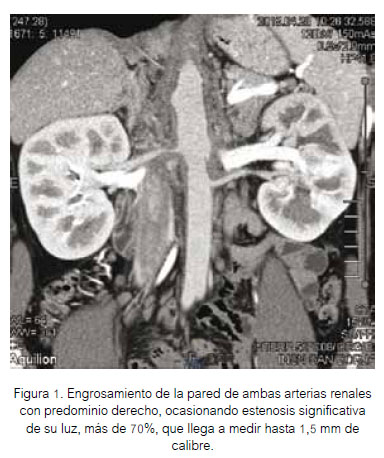

Se obtuvo angiorresonancia abdominal y cerebral seis días después del ingreso al servicio. Los hallazgos a nivel de aorta abdominal y arteria renal se presentan en las Figuras 1 y 2. No se encontraron alteraciones en arterias cerebrales.